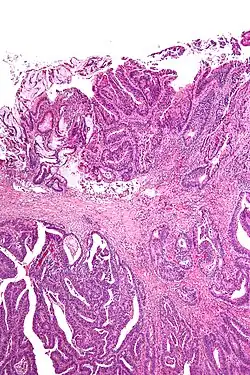

Apart from traditional methods looking at stained "shaves" (thin slices of tissue removed from the edge of the margin) or smeared and stained imprints, more recent techniques used to assess margins include x-rays with compression, frozen specimens, and new techniques such as intraoperative fluorescence imaging, Raman spectroscopy, optical coherence tomography and quantitative diffuse reflectance spectroscopy.[3][1]: sections 5-6

Surgical margin in a surgery report defines the visible margin or free edge of "normal" tissue seen by the surgeon with the naked eye. Surgical margin as read in a pathology report defines the histological measurement of normal or unaffected tissue surrounding the visible tumor under a microscope on a glass mounted histology section.[4][5] A "narrow" surgical margin implies that the tumor exists very close to the surgical margin, and a "wide" surgical margin implies the tumor exists far from the cut edge or the surgical margin. Narrow surgical margin using the bread loafing technique suggests that residual cancer might be left due to false negative error. A surgeon often will perform a second surgery if a narrow surgical margin is noted on a pathology report.

Associated errors and recurrence rate

This determination is made with the full understanding of "false negative error" intrinsic in the bread loafing technique of histology (also known as POMA - a term used by the NCCN).[6] The higher the false negative error is, the higher the recurrence rate of a cancer or tumor at the surgical margin. This is due to the misreading of a pathology specimen as being clear of residual tumor when there is actually residual tumor left where the specimen was not cut and mounted on the histology slide. The "false negative error" is very low in the CCPDMA method of histology processing, and can be very high in the bread loafing (POMA) method of histology processing.[6] In the bread loafing method of processing, one will note a high false negative error rate with narrow surgical margin; and one will note a low false negative error with a wide surgical margin[7] Surgical margin has a much less significant effect on the false negative error rate of CCPDMA methods, allowing the surgeon to routinely use very narrow surgical margins (1 to 2 mm for non-melanoma skin cancer).[7] The worldwide extent of inadequate resection of the tumor is illustrated in following Table showing the percentage of positive surgical margins for the most common cancer types.